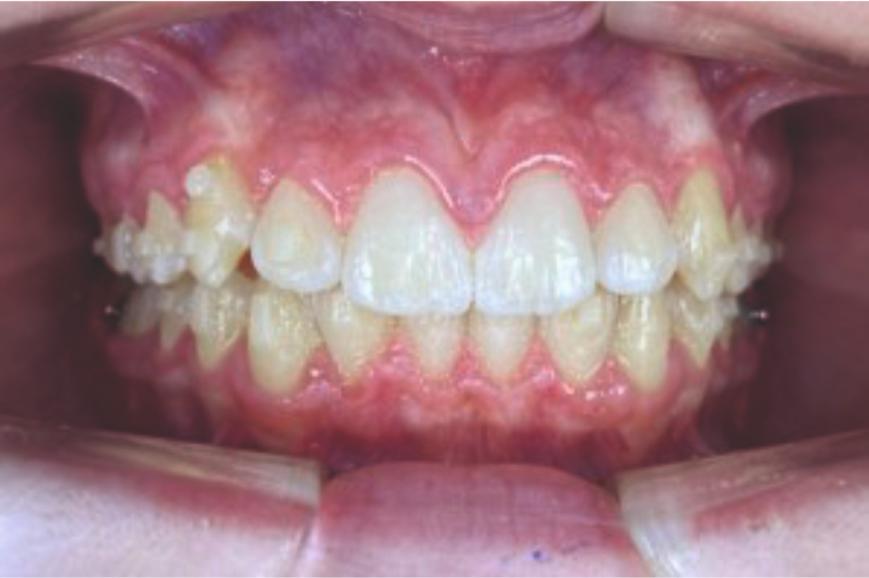

Chief complaint: We present the case of a 12-year-old female patient who came for an orthodontic evaluation, motivated by a family history of treatment. Clinical and radiographic analysis revealed a skeletal Class II malocclusion with molar and canine relationships also in Class II, moderate crowding in both arches, a deviation of the dental midline, and ectopic eruption of tooth 13. No functional issues with breathing or swallowing were observed, and oral health was generally good. A slight mandibular retrusion was noted in the soft tissue profile. A treatment plan was proposed using the Angel Aligner Pro system, aiming to correct dental misalignments and improve facial harmony through a minimally invasive, growth-adapted approach.

Clinical examination and diagnosis

- Woman ; 12/3 years

- Skeletal Class II

- Molar and canine Class II

- Upper and lower dentoalveolar compression

- Increased overjet and overbite

- Upper midline deviated 0,5 mm to the right

- Moderate upper and lower crowding